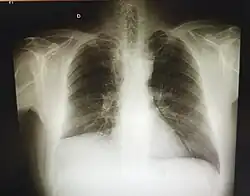

La neumonectomía consiste en la extirpación quirúrgica total o parcial de uno o ambos pulmones. La neumonectomía parcial, también conocida como lobectomía pulmonar, consiste en la extirpación de una sección pulmonar (lóbulo). La operación se practica, casi siempre, como tratamiento del cáncer de pulmón, aunque puede ser necesaria una lobectomía en algunos casos de tuberculosis, bronquiectasias o absceso pulmonar.